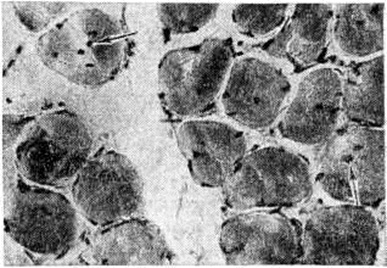

МиопатияМиопатия (греческий mys, my[os] мышца + -pathos страдание, болезнь) — группа наследственных заболеваний мышц, основными клиническими проявлениями которых являются мышечная слабость, атрофия, снижение мышечного тонуса, снижение или отсутствие сухожильных рефлексов, изменение биоэлектрической активности мышц. Первые клинико-морфологически описания заболеваний этой группы принадлежат Г. Дюшенну, Ж. Крювелье (1853), В. Эрбу (1883—1884), В. К. Роту (1876, 1895). Патология встречается во всех странах мира. Частота различных форм составляет 2—6 на 100 000 населения. Классификация Вопросы классификации Миопатия разрабатываются в различных направлениях. Миопатия классифицируют по типу наследования: аутосомно-рецессивные, аутосомно-доминантные, рецессивные и доминантные, сцепленные с Х-хромосомой. В зависимости от времени появления первых симптомов и характера течения Миопатия под разделяют на врождённую непрогрессирующую Миопатия и прогрессирующую мышечную дистрофию (ранняя детская, детская, юношеская и поздняя формы). Прогрессирующая мышечная дистрофия также подразделяется на формы в зависимости от преимущественной локализации миодистрофического процесса (например, плече-лопаточно-лицевая миодистрофия Ландузи — Дежерина, тазоплечевая миопатия Эрба — Рота, бульбарно-офтальмоплегическая Миопатия, дистальная Миопатия), характера распространения процесса восходящий и нисходящий варианты). В отдельную группу выделяют Миопатия с выраженной псевдогинертрофией мышц (псевдогипертрофическая миопатия Дюшенна, доброкачественная псевдогипертрофическая миопатия Беккера и другие). Этиология и патогенез Причиной заболеваний являются генетически детерминированные дефекты метаболизма мышечной ткани или структуры мышечных клеток. Поскольку первичный молекулярный дефект не известен ни для одной из форм Миопатия, патогенез детально не изучен. По-видимому, он не однозначен для всех форм Миопатия Известно, однако, что при всех заболеваниях этой группы в большей или меньшей степени выражены усиленный распад мышечных белков, преобладающий над их ускоренным, но неполноценным синтезом, изменения сосудов, нарушения проницаемости их стенок, нарушения структуры и проницаемости клеточных мембран, сдвиг обмена катионов, изменения в соединительной ткани и другие Предполагают, что при некоторых формах первичный молекулярный дефект локализуется не в самой мышечной ткани (а, например, в нервной) и служит лишь пусковым фактором указанных изменений. Возможно также, что при некоторых формах Миопатия эффект мутантного гена более генерализован и распространяется на мышечную, нервную и другие ткани. Патологическая анатомия Морфологически изменения при Миопатия характеризуются нарастающей атрофией скелетных мышц, которые уменьшаются в объёме и становятся плотными, бурого цвета вследствие разрастания соединительной ткани или, напротив, увеличиваются в объёме за счёт жировой клетчатки. При различных формах мышечных дистрофий (псевдогипертрофических, плече-лопаточно-лицевой, тазоплечевой, офтальмоплегической, бульбарно-офтальмоплегической) определяются в основном однотипные гисто л. изменения (рисунок 1): уменьшение количества мышечных волокон в пучках, резкая диффузная разнокалиберность сохранившихся волокон с преобладанием среди них атрофированных, гиалиновая и вакуольная дистрофия в части мышечных волокон, дискоидный и коагуляционный некроз отдельных волокон, расщепление гипертрофированных волокон, разрастание соединительной и жировой ткани в эндо и перимизии. В некоторых мышечных волокнах находят саркоплазматические тельца, саркоплазматические массы, кольцевидные миофибриллы. Изредка встречаются регенерирующие волокна с круглыми сочными ядрами и богатой рибонуклеопротеидами саркоплазмой. Мышечные веретена длительное время остаются неизмененными. В части наблюдений выявляются периваскулярные лимфоидно-гистиоцитарные инфильтраты. По мере нарастания двигательных нарушений отмечается постепенное уменьшение количества мышечных волокон и нивелировка их диаметра за счёт резкого уменьшения количества и калибра гипертрофированных волокон. |

С последней особенностью связывают длительную компенсацию двигательных нарушений у таких больных. В далеко зашедшей стадии Миопатия определяются небольшие островки из атрофированных мышечных волокон на фоне резкого склероза и липоматоза эндои перимизия (рисунок 2), при этом гистологически не представляется возможным дифференцировать Миопатия с нейромышечной атрофией. У пробандов при биопсии мышц находят единичные атрофированные мышечные волокна преимущественно I типа, пролиферацию ядер с переходом их в центр волокна и незначительное увеличение соединительной ткани в эндомизии.

Миотубулярная (центронуклеарная) Миопатия, характеризующаяся тем, что 30—85% мышечных волокон содержат центрально расположенные ядра, вокруг которых отсутствуют миофибриллы (рисунок 8); в целом такие волокна напоминают миотубулы мышц плода, что послужило основанием для предположения о том, что в основе заболевания лежит отсутствие созревания и дифференцировки мышечной ткани.